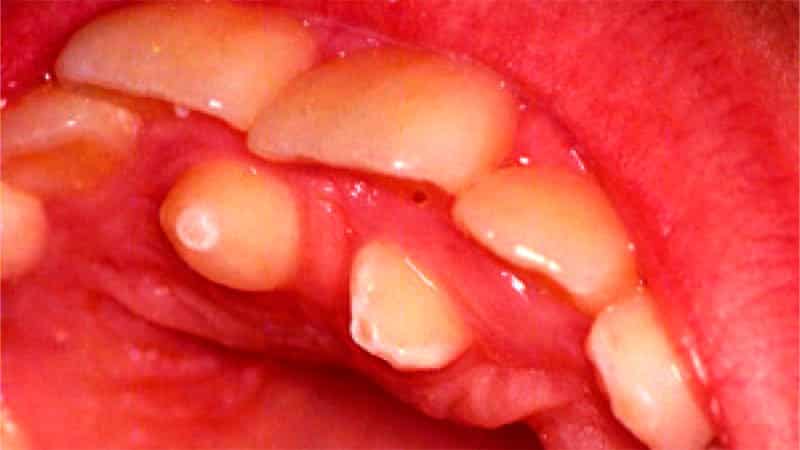

Дистопированным называют неправильное положение одного или нескольких зубов в челюсти. Это может проявляться в виде их прорастания не на положенном месте, под неправильным углом или даже с поворотом в обратную сторону. Такое состояние может привести к нарушениям прикуса или искривлению всего зубного ряда, что, в свою очередь, негативно сказывается на эстетике улыбки.

Часто врачи сталкиваются с наличием обоих этих дефектов одновременно. Наиболее распространено это явление среди зубов мудрости, которые также известны как третьи моляры. Дистопированный ретинированный зуб мудрости, изображение которого представлено ниже, является довольно распространенной проблемой. Он может вызывать такие осложнения, как пародонтоз, периодонтит, кариес и даже воспалительные процессы в полости рта.